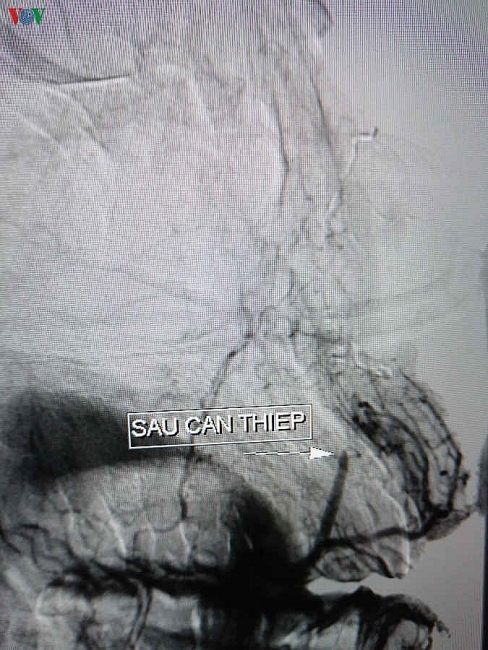

Bệnh viện Đa khoa Trung ương cho biết, các bác sĩ Khoa Tai Mũi Họng và bác sĩ can thiệp mạch bệnh viện vừa can thiệp thành công một trường hợp chảy máu mũi tái phát kéo dài 15 ngày.